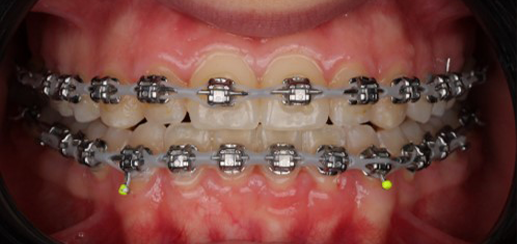

At the end of treatment, the patient’s occlusion was corrected to Class I molar and canine relationships with a physiological overjet and overbite. Irregularities in both arches were eliminated, arch forms were coordinated, and incisor torque was effectively controlled to position the roots centrally within the alveolar bone, enhancing stability. Satisfactory intercuspation was achieved in both the anterior and posterior segments, with maintenance of midline coincidence and periodontal health throughout treatment. The case was finished and transitioned into the retention phase using fixed retainers in the maxillary and mandibular anterior regions.

This case demonstrates that, in the Damon Ultima system, appropriate torque selection provides a rapid and efficient treatment modality, offering enhanced biomechanical control for the clinician and a shorter, more comfortable treatment experience for the patient. In particular, root movements and the finishing phase, which require meticulous management in Class III cases, were completed in a predictable and efficient manner, with high levels of comfort for both the clinician and the patient through the use of carefully selected torque prescriptions.